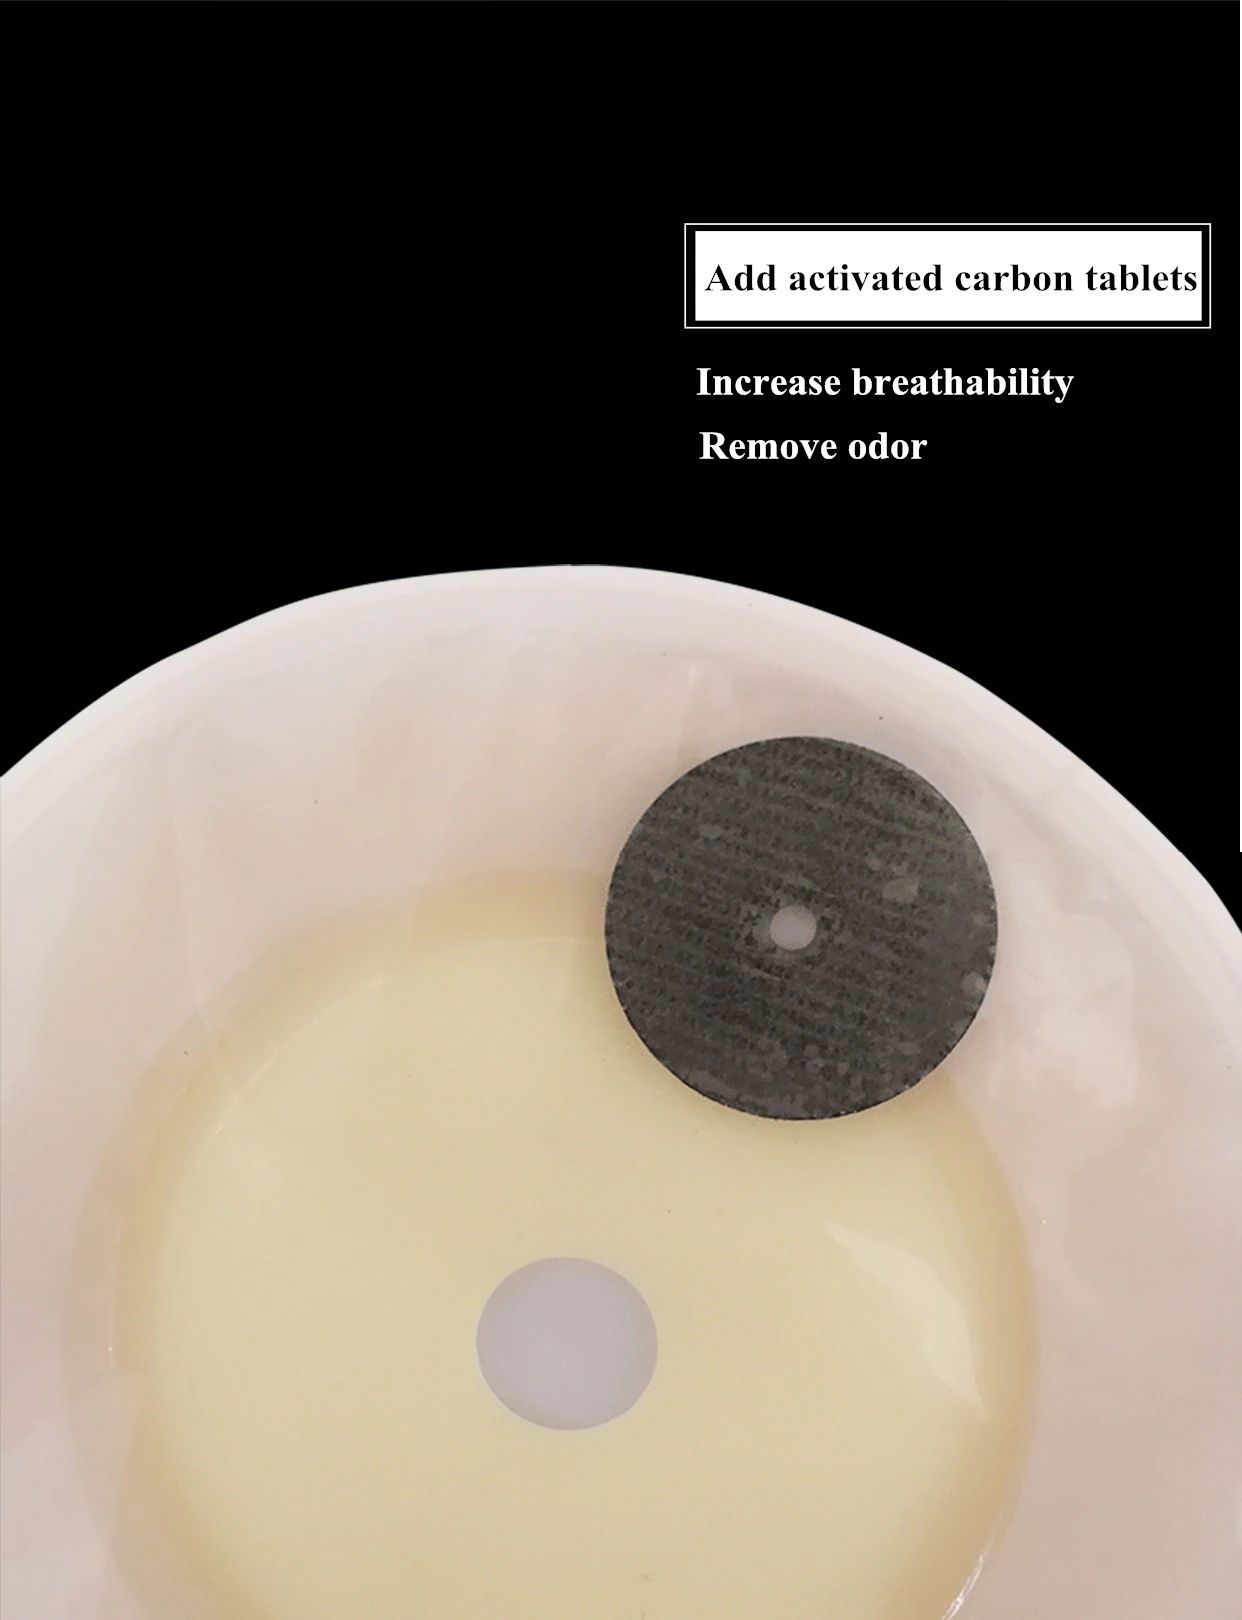

Descripción del producto La bolsa de cuidado de ostomía combina la barrera de la piel y la bolsa de colección en un sistema simple y fácil de administrar, proporcionando una gran simplicidad. La bolsa de colostomía es fácil de aplicar con el cierre de Velcro adjunto, proporcionando seguridad, ya que los sujetadores de plástico se bloquean en su lugar, fáciles de vaciar y irrigar. El propósito de reemplazar la ostomía 1. Observa la mucosa del estoma, las suturas circundantes y la piel circundante. 2. Limpia la piel alrededor del estoma, reduce el olor y aumenta la comodidad. 3. Evita que el agua fecal contamine la incisión abdominal a través de la fuga del chasis. 4. Si hay impregnación, asegúrese de reemplazarla a tiempo. Se recomienda cambiar el tiempo de 3-5 días para garantizar una respiración efectiva de la piel. Sentido común de la vida ostomía 1. Comer uniformemente, beber mucha agua y comer más verduras y frutas. 2. Evite comer demasiado rápido y tragar aire, masticar alimentos lentamente, Evite hablar mientras come, evite comer demasiado de una vez. 3. Evite las comidas con alto contenido de fibra y evite el bloqueo del estoma. 4. La ropa es suave y cómoda. 5. Evita el trabajo para aumentar la presión abdominal (como extraer objetos pesados). 6. Mantenga su estado de ánimo feliz. Paquete 10 unids/caja bolsa de ostomía